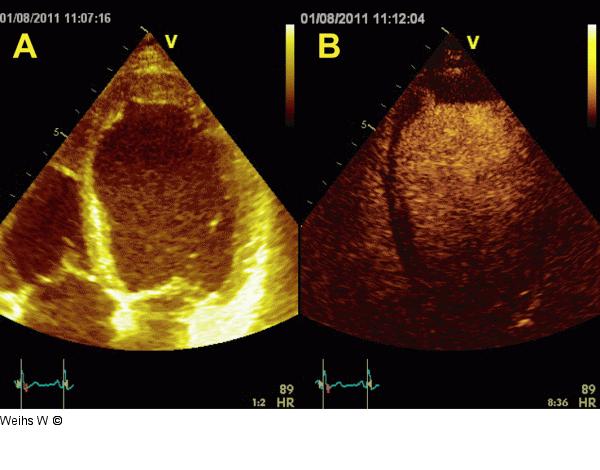

Abbildung 4a-b: Vierkammerblick Apikaler Vierkammerblick ohne (a) und mit (b) Kontrastmittel. Darstellung eines apikalen wandständigen Thrombus. Es liegt eine A- bis Dyskinesie der apikalen Segmente und eine Akinesie des mittleren anteroseptalen Segmentes vor. |

Apikaler Vierkammerblick ohne (a) und mit (b) Kontrastmittel. Darstellung eines apikalen wandständigen Thrombus. Es liegt eine A- bis Dyskinesie der apikalen Segmente und eine Akinesie des mittleren anteroseptalen Segmentes vor. |